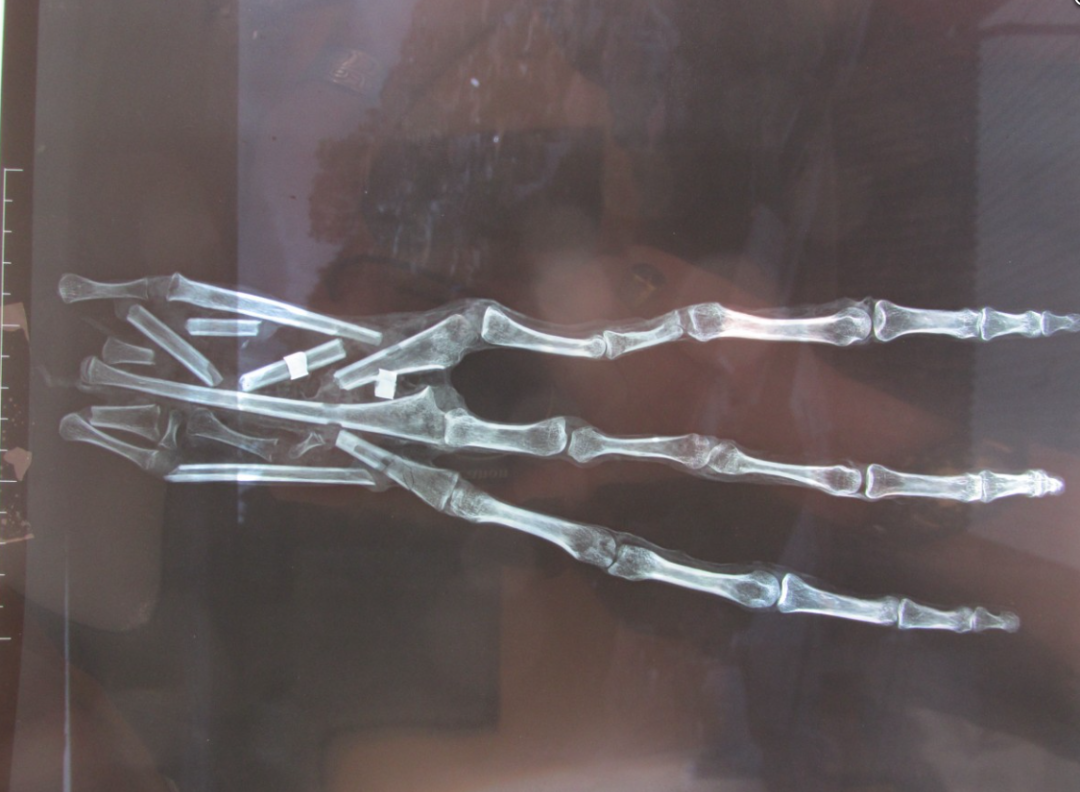

對這些外星人手腕的掃描後,結果就更離譜了。這些外星人的手部完全是用人類和動物骨骼胡亂拼接的,裏面甚至混雜了大量無意義的碎骨,有些指骨甚至是完全顛倒的。顯然,通過對人類和動物骨骼的打磨和重新拼接,有人制造了這些完全虛假的“外星人木乃伊”。

▲完全沒有任何章法的拼接手掌